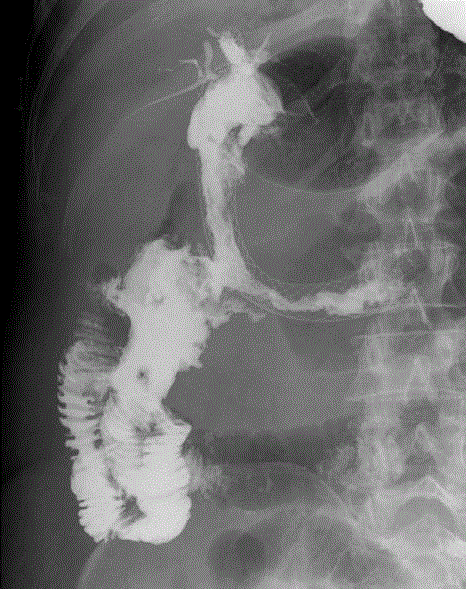

Figure 8. Duodenoenteric fistula.